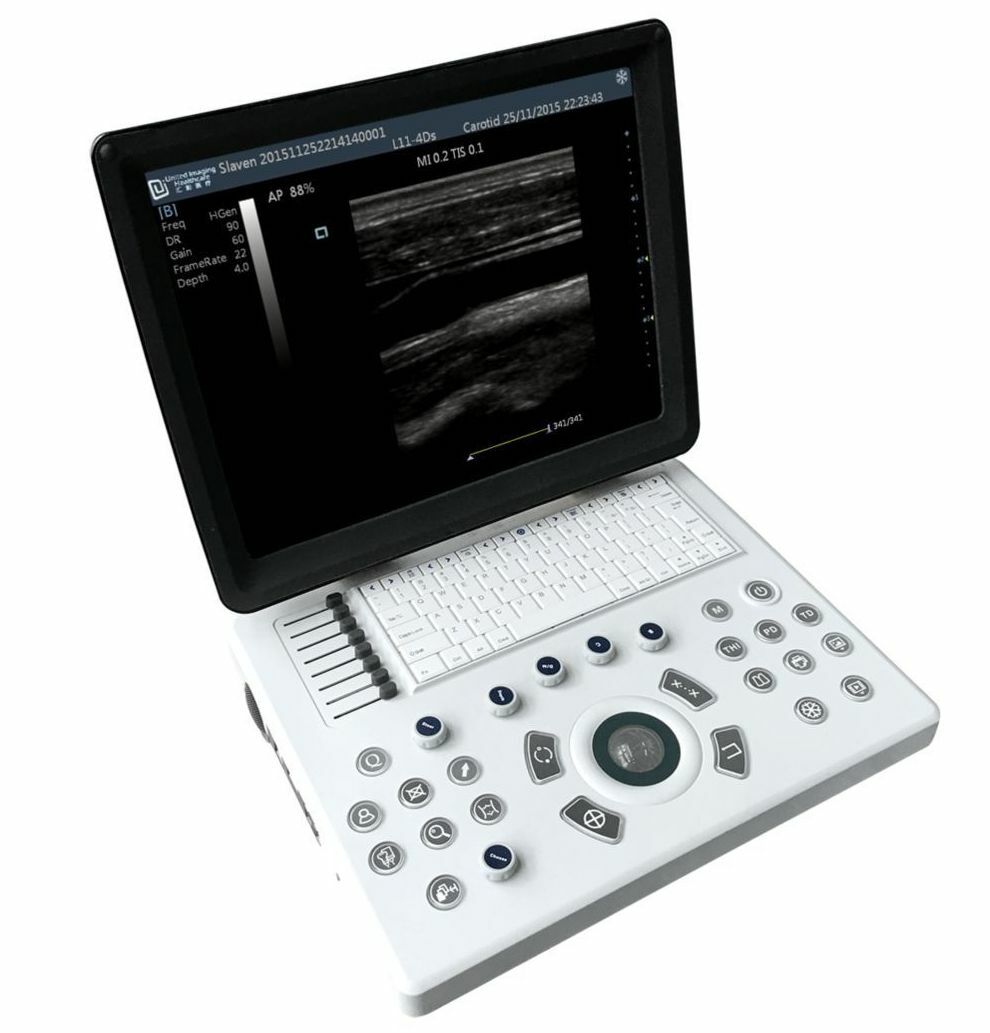

New Generation Laptop Veterinary Ultrasound 15" Screen & Rectal Probe, Keebomed

New Generation Laptop Veterinary Ultrasound 15" Screen with Rectal Probe

iuStar100Vet

This is new generation of the ultrasounds with a new type of technology that make the image better and lowers the price.

The iuStar100Vet BW is a lightweight, hand-carried black and white scanner ideal for a small animal, equine or mixed practice. It offers advanced UniView (speckle reduction) and UniCT (spatial compounding) in standard configuration. The screen on the system is 15” and can be angled up or down, this is a really useful function when scanning at different heights.

Monitor

- 15-inch high resolution LED monitor

- Resolution: 1024 ×768

User Interface

- Control panel

- User-centric control panel

- Backlit keys ensure accurate work in the dark room

- 8-segment TGC control

- Full-sized, QWERTY keyboard for text input, function keys and system programming

Linear(L40): L11-4Ds